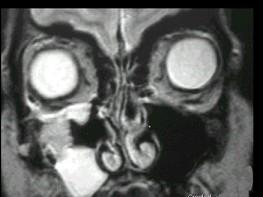

问题 女性,50岁,右鼻塞、脓涕3个月,CT、MRI检查如图所示,请选择正确的答案 ( )

选项 A、右侧上颌窦黏液腺瘤 B、右侧上颌窦腺样囊性癌 C、右侧上颌窦粘膜下囊肿 D、右侧上颌窦积液 E、右侧上颌窦黏液囊肿

答案 B